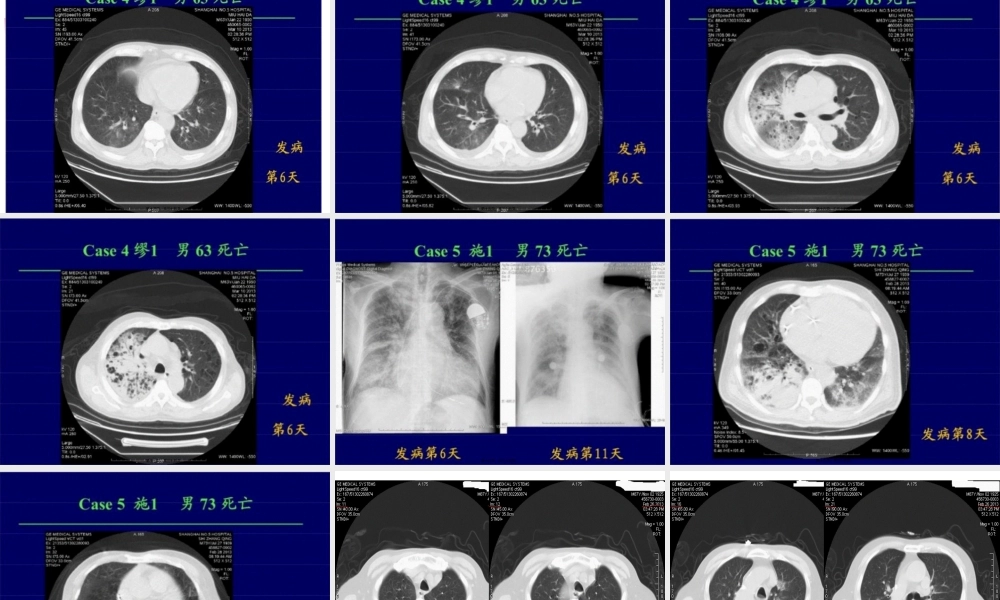

人感染H7N9禽流感知识介绍第一页,共三十五页。由H7N9亚型禽流感病毒引起的急性呼吸道传染病。属甲型流感病毒亚型。目前尚无确切证据显示此次的H7N9病毒可以通过人与人之间传播。因此目前在人群中传播力不强。第二页,共三十五页。病原学禽流感病毒,属正粘病毒科甲型流感病毒属,单股负链RNA。依据其外膜血凝素〔H〕和神经氨酸酶〔N〕蛋白抗原性不同,目前可分为16个H亚型〔H1~H16〕和9个N亚型〔N1~N9〕。此次的人感染H7N9禽流感病毒。该病毒为新型重配病毒,其内部基因来自于H9N2禽流感病毒。抵抗力:对热敏感,对低温抵抗力较强,65℃加热30分钟或煮沸〔100℃〕2分钟以上可灭活。病毒在较低温度粪便中可存活1周,在4℃水中可存活1个月,对酸性环境有一定抵抗力。第三页,共三十五页。流行病学传染源。目前尚不明确,根据以往经验及本次病例流行病学调查,推测可能为携带H7N9禽流感病毒的禽类及其分泌物或排泄物。传播途径。经呼吸道传播,也可通过密切接触感染的禽类分泌物或排泄物等被感染,直接接触病毒也可被感染。现尚无人与人之间传播确实切证据。易感人群。目前尚无确切证据显示人类对H7N9禽流感病毒易感。现有确诊病例均为成人。高危人群。现阶段主要是从事禽类养殖、销售、宰杀、加工业者,以及在发病前1周内接触过禽类者。第四页,共三十五页。临床表现根据流感的潜伏期及现有H7N9禽流感病毒感染病例的调查结果,潜伏期一般为7天以内。一般表现为流感样病症,如发热,咳嗽,少痰,可伴有头痛、肌肉酸痛和全身不适。重症患者病情开展迅速,表现为重症肺炎,体温大多持续在39℃以上,出现呼吸困难,可伴有咯血痰;可快速进展出现急性呼吸窘迫综合征、纵隔气肿、脓毒症、休克、意识障碍及急性肾损伤等。第五页,共三十五页。实验室检查血常规。白细胞总数一般不高或降低。重症患者多有白细胞总数及淋巴细胞减少,并有血小板降低。血生化检查。多有肌酸激酶、乳酸脱氢酶、天门冬氨酸氨基转移酶、丙氨酸氨基转移酶升高,C反响蛋白升高,肌红蛋白可升高。病原学检测。〔1〕核酸检测。对患者呼吸道标本〔如鼻咽分泌物、口腔含漱液、气管吸出物或呼吸道上皮细胞〕采用realtimePCR〔或RT-PCR〕检测到H7N9禽流感病毒核酸。〔2〕病毒别离。从患者呼吸道标本中别离H7N9禽流感病毒。第六页,共三十五页。胸部影像学检查发生肺炎的患者肺内出现片状影像。重症患者病变进展迅速,呈双肺多发磨玻璃影及肺实变...